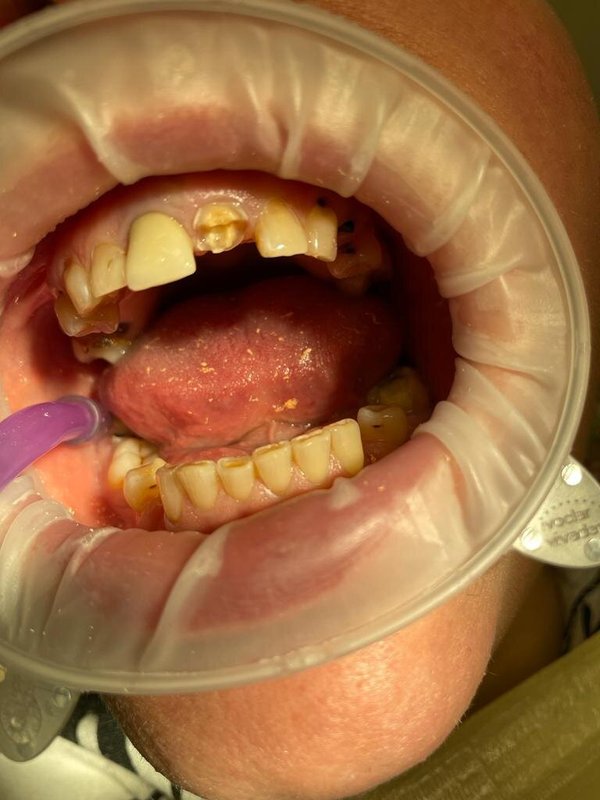

Фотогалерея